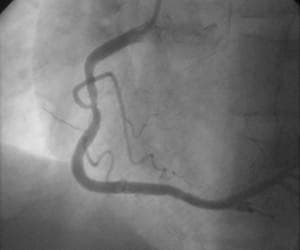

EKG, Kalbin elektriksel aktivitesinin özel kâğıtlara yazdırılma işlemine elektrokardiyografi (EKG) denilmektedir. Kalbin elektriksel aktivitesi deriye yerleştirilen küçük metal diskler (elektrotlar) vasıtasıyla ölçülmektedir. Elektrotlar hastanın göğsüne, kollarına ve bacaklarına yerleştirilmektedir. Elektrotlar, elektriksel aktiviteyi kağıt üzerindeki şekle dönüştüren cihaza bağlanmaktadır.

Kağıt üzerindeki bulgular da hekimler tarafından değerlendirilmektedir. Elektrokardiyografi kalp genişlemesi, kalp büyümesi, kalbe giden kan miktarındaki azalma, yeni veya eski kalp hasarları, kalp ritim problemleri ve değişik kalp ve kalbi saran zar hastalıkları hakkında önemli bilgiler verebilmektedir.